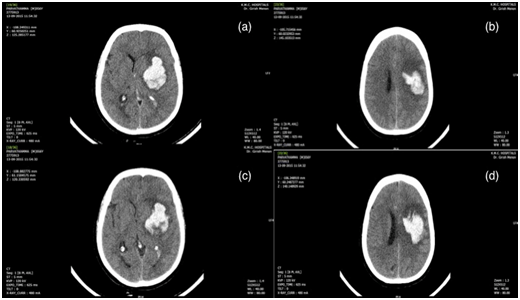

A 65-year-old lady presented with sudden onset of loss of consciousness and right-sided weakness. She was a hypertensive on regular treatment but had no other co-morbidities. On admission, she was intubated and had a GCS of E2M5, stable vitals, and a right hemiplegia. Her CT scan showed a large left putaminal bleed with intraventricular extension and early hydrocephalus (Figure 3) (SICH score 3). After explaining the risks involved, the patient was taken up for an immediate craniotomy and evacuation of the haematoma under GA. The patient was electively ventilated post procedure and started on decongestants. The repeat CT brain done next day showed an evolving infarct over the left ICA territory with oedema (Figure 4) elevating the bone flap and complete effacement of the basal cisterns. She was then immediately taken up for an emergency decompressive craniectomy. Post procedure she was sedated and electively ventilated with decongestants. The post op scan showed a large patchy ICA infarct on the left side with oedema and trans calvarial herniation of the brain through the decompressive craniectomy site. Thereafter, she had a stormy course and was discharged nearly two weeks after the surgery in a vegetative state.

Figure 4 Postoperative axial CT scan showing an evolving infarct over the left ICA territory with oedema and complete effacement of the basal cisterns (a to d).